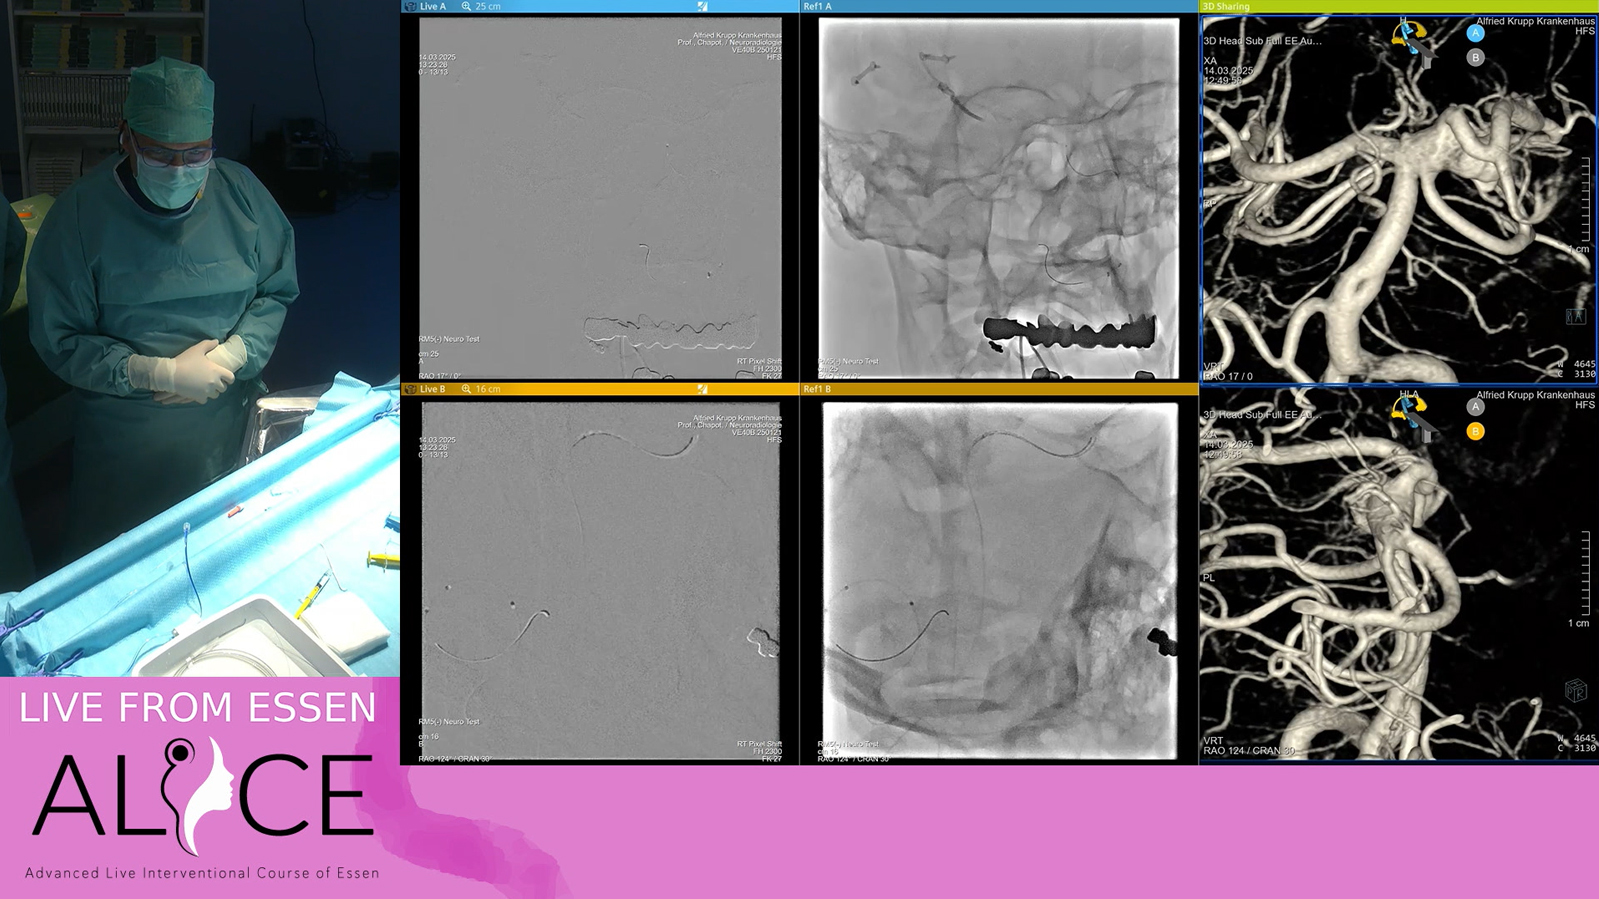

MCA Aneurysm treated by balloon & comanecci assisted coiling and Stenting with Baby Leo

Watch the video